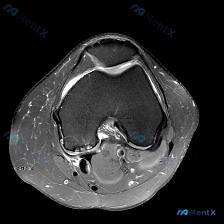

看到一份踝关节MRI的读片资料,整理了完整的分析和鉴别思路分享给大家。 病例核心影像信息 这是踝关节上方水平的轴位T2序列MRI: 1. 解剖层面:显示踝穴上方的胫骨远端干骺端、腓骨远端,可清晰识别跟腱、胫骨后肌腱、趾长屈肌腱、踇长屈肌腱、腓骨长短肌腱等结构 2. 核心阳性发现:内踝后方胫骨后肌腱的...